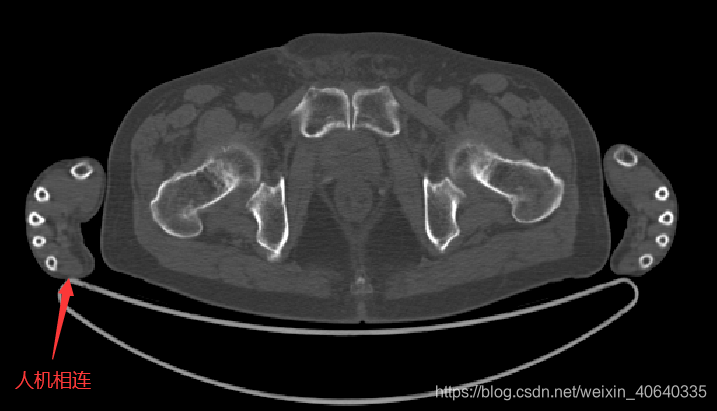

不理想的情况指的是,人体与机床有相连,导致取连通域后得到的mask其实包含有机床部分,这种情况在实际中也经常碰到,因此需要去除机床部分,尝试了以下两种方法:

机床MASK示例:

红色部分就是机床mask了,结果还不错,再配合最开始的方法,获得人体的mask

人体MASK示例: